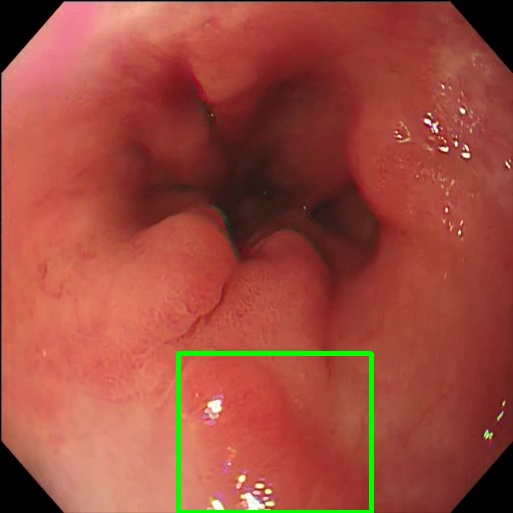

Gaussian Blur

Endoscopy GMAIMMbench Disease Diagnosis

Gaussian Blur - L0 (Original)

L0

L0 (Original)

Gaussian Blur - L1 (Moderate)

L1

L1 (Moderate)

Gaussian Blur - L2 (Severe)

L2

L2 (Severe)

Question

Focus on the square-highlighted area of this endoscopy image. What could be the potential diagnosis?

A barrett's esophagus B high-grade dysplasia C polyp D gastrointestinal tract cancer

Ground Truth: D. gastrointestinal tract cancer